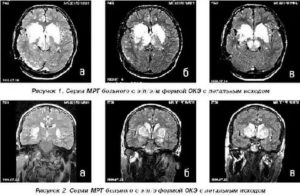

Результаты МРТ исследования врач-диагност получает в трехмерных срезных снимках мозга, а пациент получает изображение на носителе или на почту.

МРТ головного мозга здорового человека показывает целостный орган, без патологических очагов и смещений структур.

Описание заболеваний на сканировании:

МРТ при опухоли.

На снимке новообразование имеет вид несимметричного белого большого пятна, которое имеет рваные края. Это пятно может смещать соседние структуры головного мозга, из-за чего на снимке желудочки и пространства уменьшаются в размере. Когда растет опухоль, появляются новые сосуды. Это видно на ангиографической магнитной ангиографии.

Инсульты.

Ишемический инсульт – это область мозга, где недостает крови. Так, на снимке эта зона выделяется более светлым участком, в отличие от соседних зон. Однако в отличие от новообразования, это светлое пятно будет располагаться в области магистрального сосуда. Если применить ангиографию, то в области ишемии контрастирование снижается.

Геморрагический инсульт – это кровоизлияние в мозговое вещество. На снимке это выглядит как затемнение на МРТ в области магистральной артерии, окруженный темной полосой.